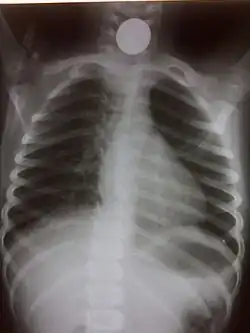

Chest radiograph showing a Venezuelan 25 cent coin lodged in the upper esophagus of a 9-year-old girl. -

A coin seen on AP CXR in the esophagus -